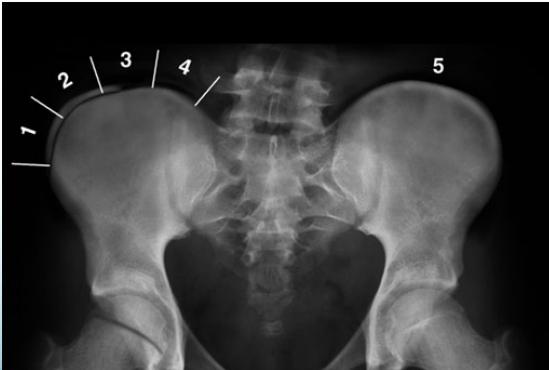

Risser’s Sign

- Measures potential for growth progression

- Ranges from 0 (no ossification) to 5 (complete bony fusion)

- Lower grade = Higher progression potential

Growth Assessment: Risser Grading

- Measures bony fusion of iliac apophysis

- Range: 0 (no ossification) to 5 (complete bony fusion)

Imaging

- X-ray:

- AP and LAT of entire spine (Cobb angle measurement)

- AP pelvis (Risser grade)